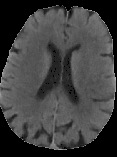

Accurate infarct segmentation in non-contrast CT (NCCT) images is a crucial step toward computer-aided acute ischemic stroke (AIS) assessment. In clinical practice, bilateral symmetric comparison of brain hemispheres is usually used to locate pathological abnormalities. Recent research has explored asymmetries to assist with AIS segmentation. However, most previous symmetry-based work mixed different types of asymmetries when evaluating their contribution to AIS. In this paper, we propose a novel Asymmetry Disentanglement Network (ADN) to automatically separate pathological asymmetries and intrinsic anatomical asymmetries in NCCTs for more effective and interpretable AIS segmentation. ADN first performs asymmetry disentanglement based on input NCCTs, which produces different types of 3D asymmetry maps. Then a synthetic, intrinsic-asymmetry-compensated and pathology-asymmetry-salient NCCT volume is generated and later used as input to a segmentation network. The training of ADN incorporates domain knowledge and adopts a tissue-type aware regularization loss function to encourage clinically-meaningful pathological asymmetry extraction. Coupled with an unsupervised 3D transformation network, ADN achieves state-of-the-art AIS segmentation performance on a public NCCT dataset. In addition to the superior performance, we believe the learned clinically-interpretable asymmetry maps can also provide insights towards a better understanding of AIS assessment. Our code is available at https://github.com/nihaomiao/MICCAI22_ADN.